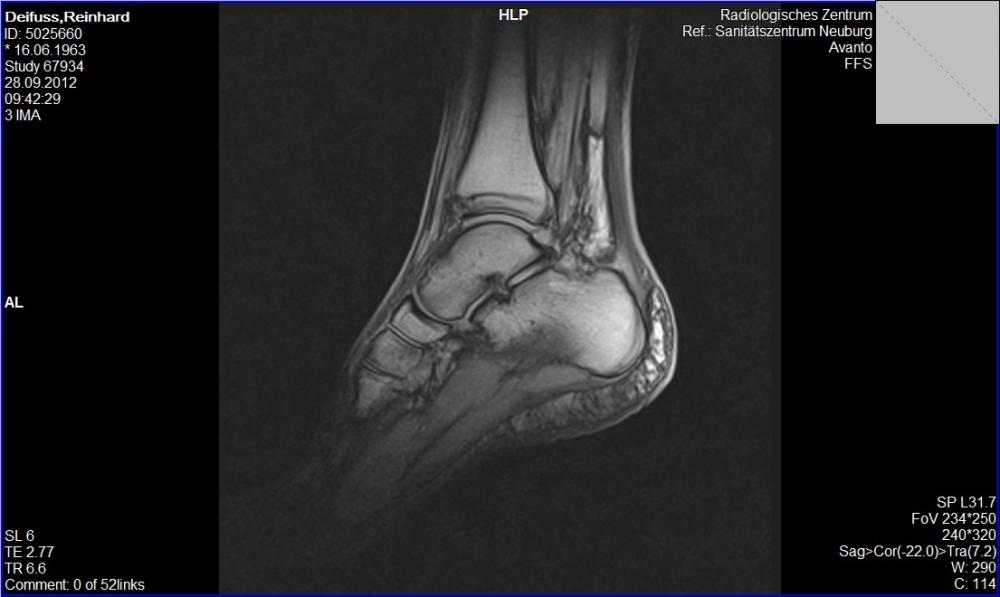

Der Kontakt zum Schienbein erfolgt über eine knorpelige Gelenkfläche, die Facies articularis capitis fibulae, die mit der Facies articularis fibularis tibiae am Condylus . Der Bewegungsapparat des Erwachsenen besteht aus passiven und aktiven Teilen.Überblick über Knochenbrüche. In seltenen Fällen kann es zur .Die andere Möglichkeit, dass ein Wadenbeinbruch (erst) unbemerkt bleibt, ist der Ermüdungsbruch, der auch Stressbruch oder Stressfraktur genannt wird.Ärztinnen und Ärzte sprechen dann von einer Sprunggelenkfraktur. Ermüdungsbrüche können zum Beispiel durch eine längere Wanderung oder beim Joggen auftreten.at-Inhalte werden von medizinischen Fachjournalisten überprüft. Diese Bilder wurde durch Dr. Häufig kommt es beim Sport zu Verletzungen, auch Brüche sind keine Seltenheit. Platten, Schrauben und ein langer Nagel halten zusammen, was zusammengehört.Eine Schienbeinprellung entsteht durch ein stumpfes Trauma (Gewalteinwirkung) auf den Knochen. Bis der Knochen wieder ausgeheilt ist, dauert es im Schnitt etwa fünf bis sechs Wochen. , MD, University of California, San Francisco. Durchschnitt: .Sprunggelenkbruch: Was hilft, wieder auf die Beine zu kommen? Nach der Operation eines Sprunggelenkbruchs kann es kurzfristig Vorteile haben, eine abnehmbare Bandage oder Schiene zu tragen und bereits nach einigen Tagen vorsichtig mit Bewegungsübungen oder Physiotherapie zu beginnen.

Wenn das Sprunggelenk gebrochen ist, sind oft auch die Bänder gerissen und der Knorpel beschädigt. Das Wadenbein fällt in seinem Umfang dünner aus als das Schienbein. Häufigste Ursachen sind neben Sportverletzungen auch Verkehrsunfälle und Stürze. beim Gehen und Stehen. Nicolas Gumpert veröffentlicht. Zu den typischen Anzeichen gehören: ©.

Dies ist eine ernsthaftere Verletzung, bei der ein oder mehrere Knochen des Sprunggelenks betroffen sein können. Als erste Maßnahme bei einem Wadenbeinbruch muss der Patient das .Auch eine Verletzung der Syndesmose (dem Band zwischen Tibia und Fibula) kann eine Ursache für Schmerzen und Schwellungen am Wadenbein sein. Eine der häufigsten Ursachen für Wasseransammlungen in den Beinen ist eine schlechte Durchblutung, die dazu führt, dass das Blut nicht richtig .